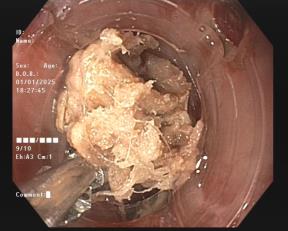

Thức ăn ứ đọng trên vị trí xương mắc và xương gà hình chạc 3 được gắp ra ngoài

Trong quá trình nội soi, các bác sĩ phát hiện tại thực quản vị trí cách cung răng trên 16 cm có dị vật xương gà hình chạc ba, dài 03 cm, sắc nhọn, đâm ngang thực quản làm ứ đọng thức ăn phía trên, thành thực quản tại vị trí xương đâm có vết rách ngắn, phủ giả mạc trắng, không thấy chảy dịch mủ. Ekip nội soi tiến hành dùng kìm gắp thành công chiếc xương ra ngoài.